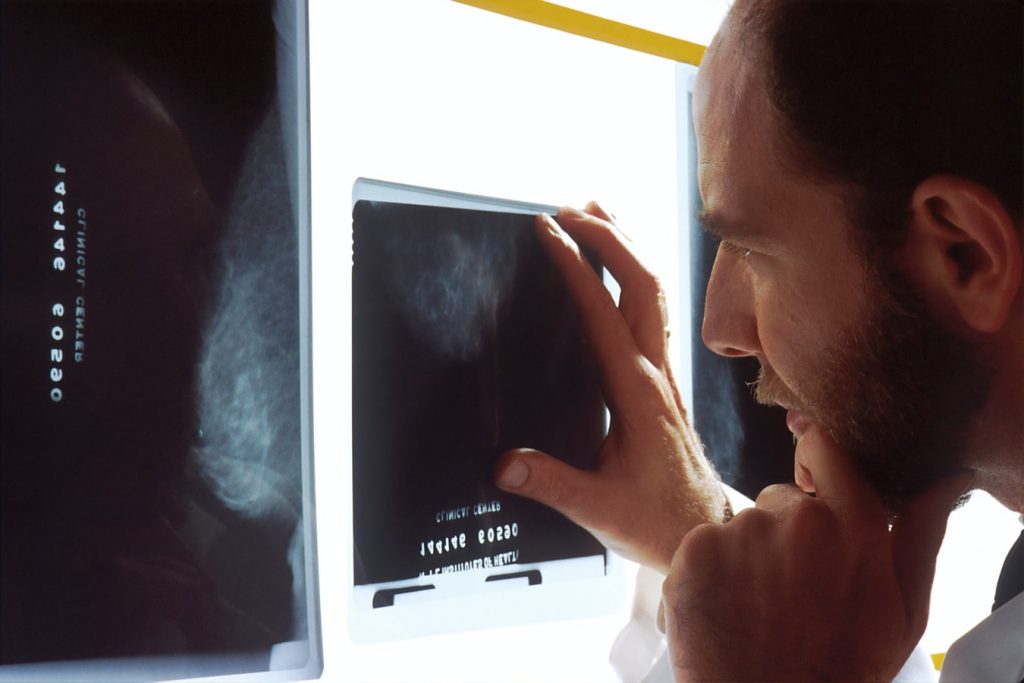

- X-ray – imaging test identifies issues with the vertebrae and joints that comprise the spine

- MRI (magnetic resonance imaging) – a 3-dimensional image that shows the spinal cord, nerve roots, and other soft tissues

- CT scan with 3-D reconstruction – a 3-dimensional image that shows greater details of the bones, nerves and soft tissues by creating cross-section views